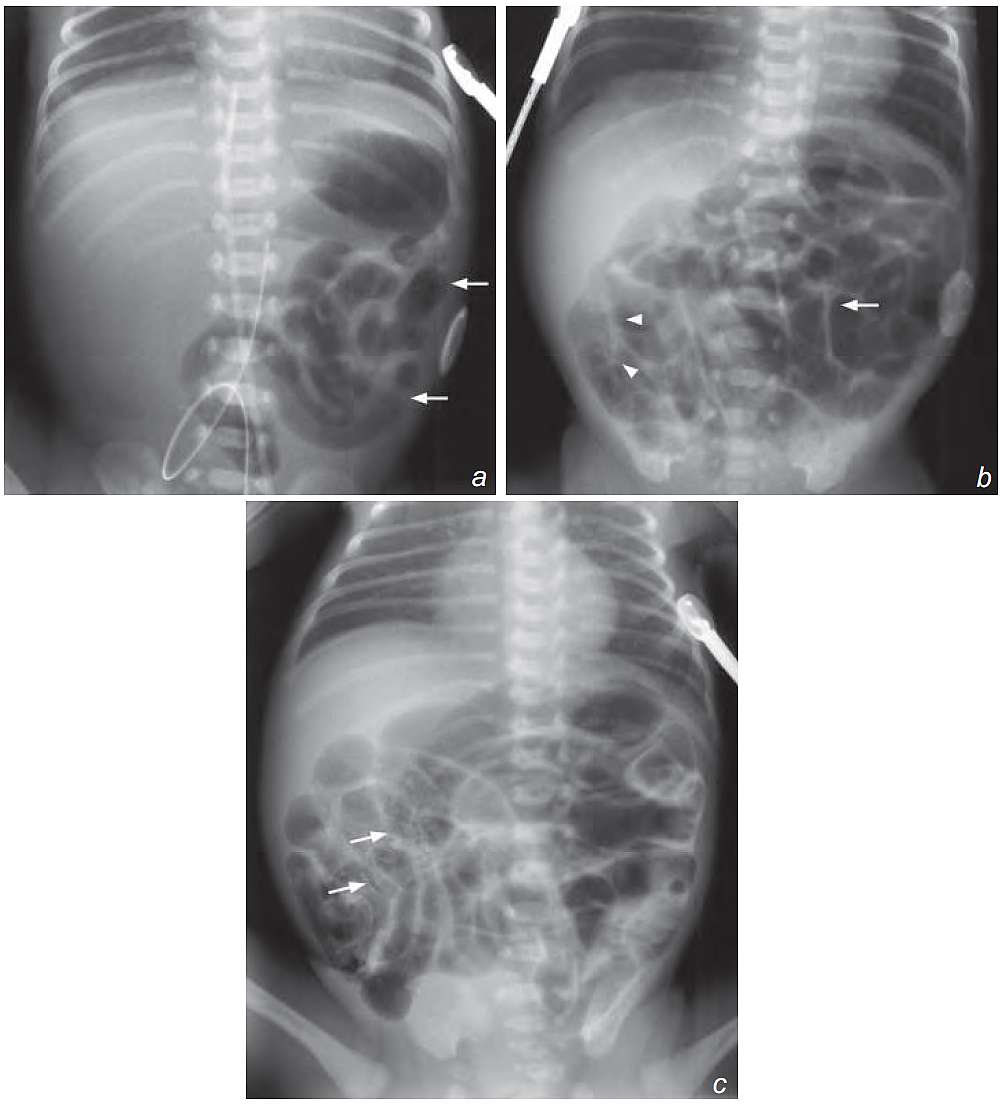

b) As the disease progresses, dilated bowel loops (arrow) are seen all over the abdomen and ‘sandy foamy’ appearance (arrowheads) due to presence of faeces and intramural gas is noted over the right lower quadrant of the abdomen.

c) Presence of intramural gas (pneumatosis intestinalis) in the ileal bowel loops over right side of the abdomen, causing a bubbly appearance in the terminal ileal loops (arrows)

- Distended bowel loops in the abdomen – represents ileus which affects terminal ileum first

- Pneumatosis intestinalis – gas within bowel wall

- Bubbly appearance of bowel – due to mixture of intramural gas and faecal material